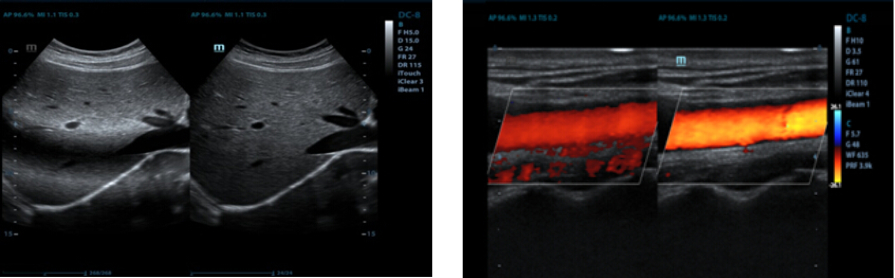

B-Steer/ iNeedle??

Alat Anda untuk biopsi lebih dalam: memungkinkan penyesuaian garis pemindaian untuk mendapatkan visibilitas lebih baik atas jarum, syaraf dan pembuluh kecil.

IMT (Intima-Media Thickness) Otomatis

Pengukuran otomatis ketebalan dinding anterior dan posterior yang memberikan status karotid dengan akurat.